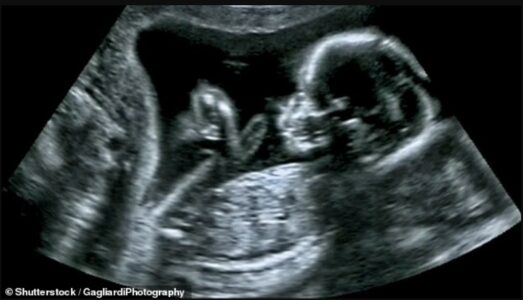

Alarm nga radiologët: Klinikat private po bëjnë eko për foshnjat me persona të patrajnuar

Shoqata e Radiografëve në Britani (Society of Radiographers – SoR) ka ngritur alarmin për rrezikun e madh që po paraqesin klinikat private të ekos për shtatzëna, të cilat shpesh operojnë pa staf të kualifikuar mjekësor.